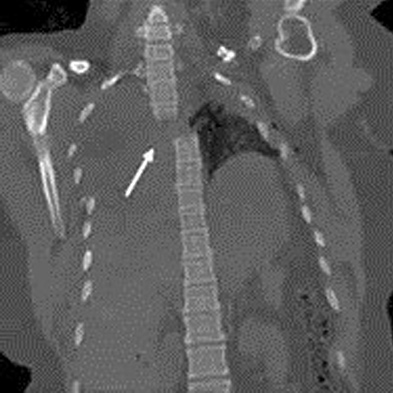

Figures 1 through 3 show the radiograph and CT images of a 68-year-old

woman who sustained a cervical injury after tripping over her cat. She has mild facial trauma, which includes a broken upper incisor and a nonsurgical nasal fracture. She is neurologically intact. Her past medical history is consistent with obstructive sleep apnea, non–insulin-dependent diabetes mellitus (hemoglobin A1c level of 9.0), and morbid obesity, with a body mass index of 40. What is the preferred treatment for this patient?

4. Anterior odontoid screw fixation Discussion: C

Posterior C1-2 fusion with instrumentation provides stability and pain relief with excellent clinical outcomes despite the loss of C1-2 motion. Hard collar immobilization and halo vest immobilization both carry a substantial risk of nonunion in this patient because of her age, fracture displacement, residual fracture gap, and medical condition. Anterior odontoid screw fixation theoretically preserves C1-2 motion. In this case, the fracture is not reduced. Concentric reduction is a requisite for osteosynthesis of the odontoid. Her body habitus also may not allow anterior odontoid fixation.